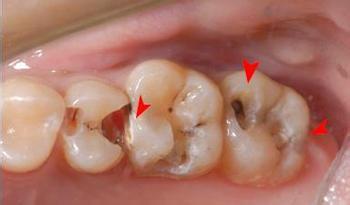

兒童乳牙容易發(fā)生蛀牙的原因有哪些?有的孩子的牙齒上有好象被蟲子蝕了的小黑洞,人們通常叫“齲齒”、“蛀牙”醫(yī)學(xué)上稱“齲齒”。齲齒不是蟲子蛀的,發(fā)生原因很復(fù)雜,可能與身體本身因素、食物因素和細(xì)菌因素有關(guān)。比如有的人從父母那里遺傳下來的牙齒和口腔的條件,就容易患齲齒;有的在胎兒時(shí)或生后的嬰幼兒時(shí)期,由于母親或嬰幼兒的食物中缺少一些形成牙齒所需要的原料,如維生素A、C、D,礦物質(zhì)鈣、磷,微量元素氟等,使牙齒結(jié)構(gòu)有所缺陷,容易受到其他不利因素的影響;孩子牙齒長得不整齊時(shí),容易藏食物殘?jiān)图?xì)菌,為齲齒的發(fā)生創(chuàng)造了條件;再者,唾液的性質(zhì)、身體某些疾病,都可影響牙齒內(nèi)外環(huán)境,構(gòu)成容易發(fā)生齲齒的因素。

齲齒的發(fā)生,是在上述因素綜合作用下產(chǎn)生的。食物中的碳水化合物,特別是糖,殘留在牙齒表面一些不易清除的地方,為細(xì)菌提供了隱藏之處和營養(yǎng),使之大量繁殖,同時(shí)將食物殘?jiān)瘮》纸�,發(fā)生化學(xué)反應(yīng),產(chǎn)生酸性物質(zhì),使牙齒表面脫鈣,發(fā)生缺損,此時(shí)細(xì)菌借機(jī)深入,并形成惡性循環(huán),于是牙齒就出現(xiàn)齲洞,形成齲齒。齲齒的發(fā)病率很高,據(jù)我國調(diào)查,大約有一半人患有齲齒且平均每人有2~3個(gè)齲齒。